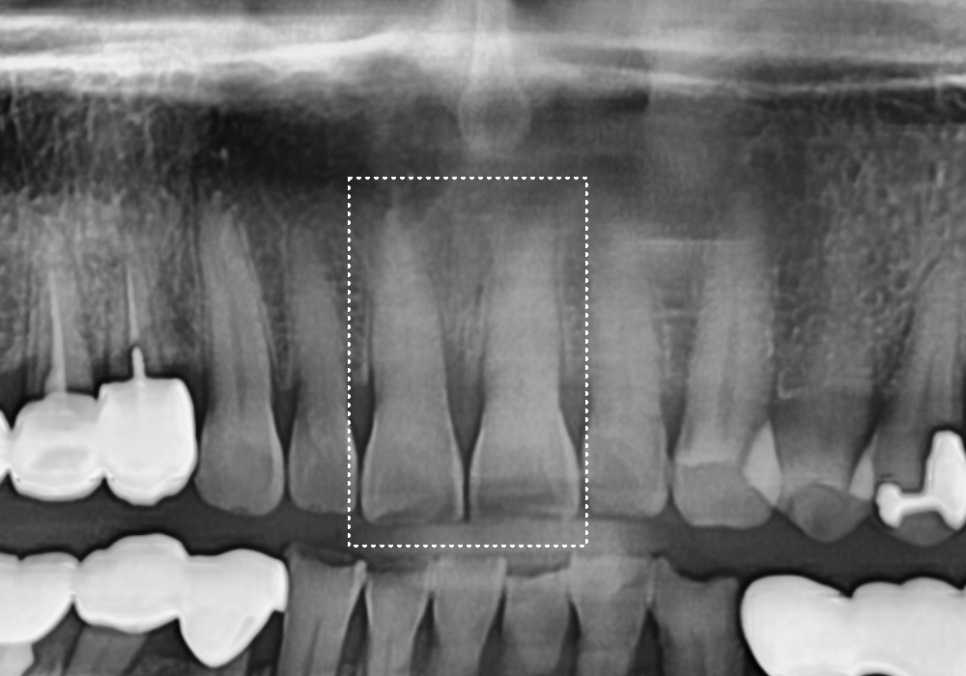

이미 치아 전체에 눈에 보이지 않는

미세한 금(Crack)이 가 있었고,

앞니 끝은 음식을 끊어내는 힘을

직접 받는 부위라

레진으로만 때우면 금방 떨어지거나

깨질 위험이 매우 컸기 때문인데요!

이런 상황에서는 치아를 전체적으로 감싸

보호해 주는 치료가 필수적입니다.

결국 안전하게 치아를 보호해 주는

지르코니아 크라운으로

치료를 도와드렸어요.